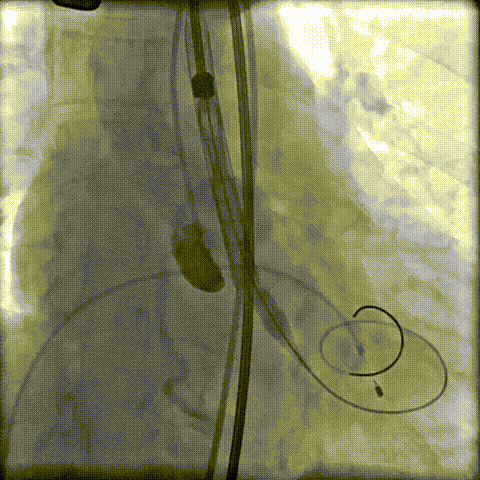

第一次定位释放

工作位瓣膜“上跳“,完全回收后二次定位